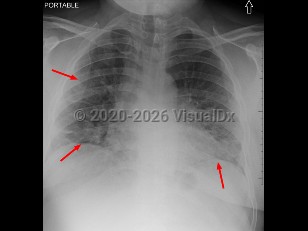

- Severe (dyspnea, hypoxia, or > 50% lung involvement on imaging)